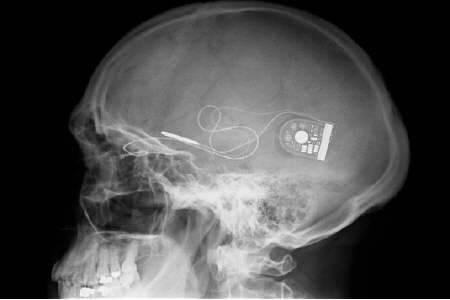

وكان المريضان كريس جيمس وروبن ميلر قد فقدا البصر بسبب حالة مرضية تعرف باسم التهاب الشبكية الصبغي، وهي حالة تتوقف فيها الخلايا المستقبلة للضوء في الجزء الخلفي من العين تدريجيا عن العمل...وتتضمن الجراحة وضع الشريحة الإلكترونية خلف الشبكية حيث توجد وصلة رقيقة تصل إلى وحدة تحكم تحت الجلد في المنطقة الواقعة خلف الأذن